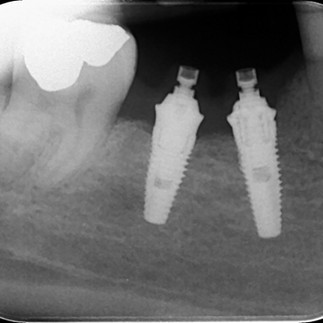

Quando gli impianti dentali vengono posizionati con tecniche "in due tempi", una volta inseriti si attendono dai 2 ai 4 mesi (in funzione della tipologia di impianto utilizzato) affinche' avvenga quel processo di guarigione denominato "osteointegrazione" in cui la fixture e l'osso alveolare si fondono. Durante questa fase viene utilizzata sulla festa della fixture una "vite tappo" o vite di chiusura (vedi radiografia sottostante). A guarigione avvenuta, l'impianto viene poi scoperto, la vite di chiusura rimossa ed al suo posto viene posizionata una vite di guarigione che ha il compito di condizionare la gengiva in modo tale che guarisca attorno ad essa, ricreando un profilo di emergenza anatomico del tutto simile a quello del dente naturale. A guarigione avvenuta dei tessuti gengivali, sarà possibile sostituire alla vite di guarigione un abutment standard o individuale, dell'altezza o del diametro corretto in funzione delle condizioni anatomiche della zona, e si prosegue con le successive fasi proteiche: